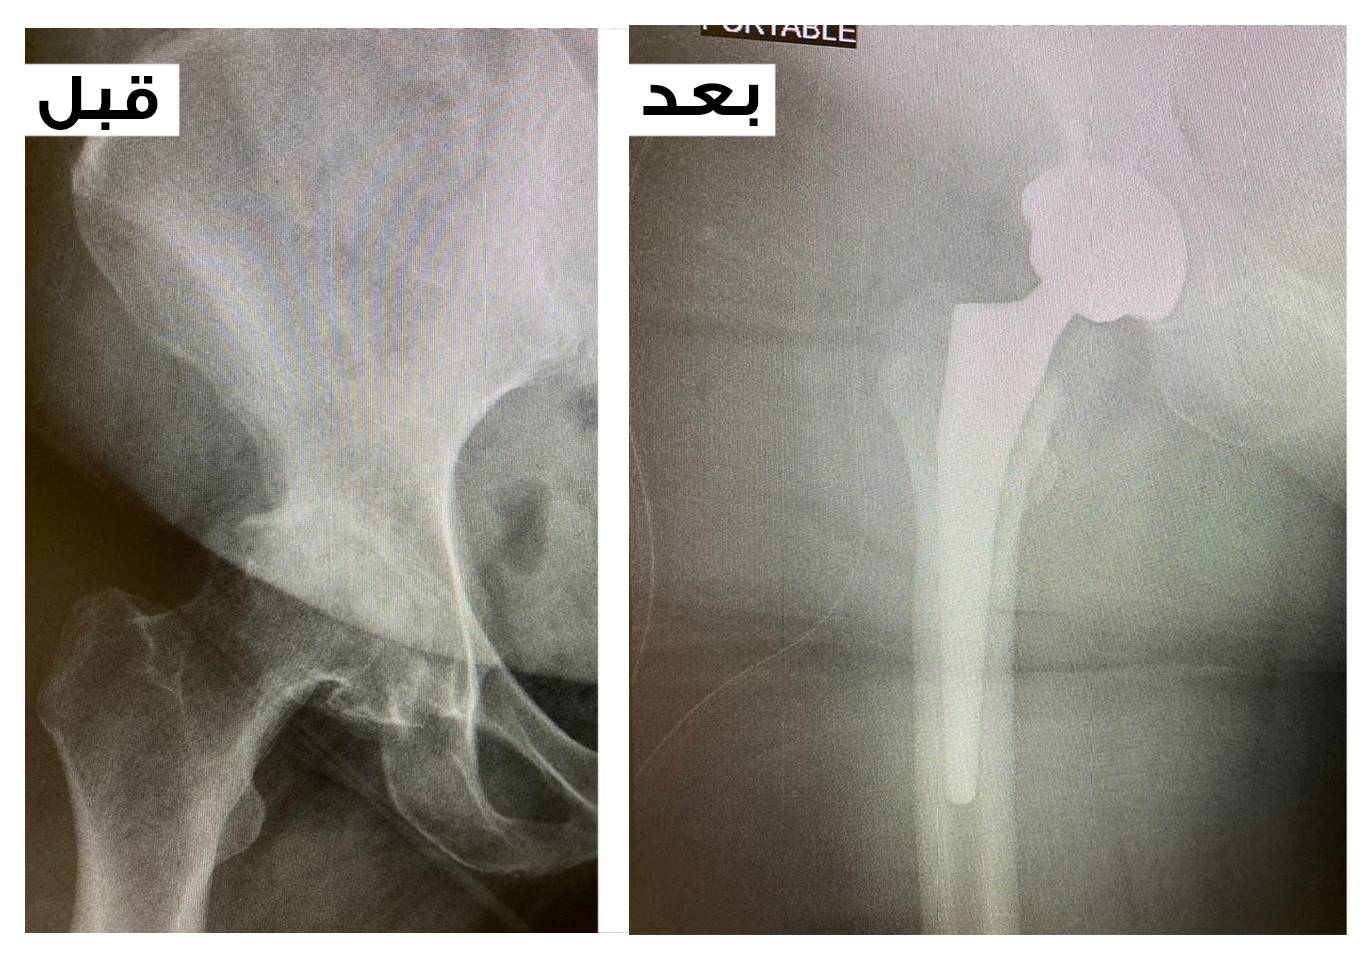

السعودي الألماني دبي یستبدل مفصل الورك لمریضة خمسینیة وزنھا 148 كج

خضعت مریضة عربیة الجنسیة لجراحة ناجحة في المستشفى السعودي الألماني دبي لاستبدل مفصل وركھا المھترئ المتآكل و نجح المستشفى في تركیب مفصل صناعي جدید لھا خلصھا من آلام مبرحة لم تعد تطیقھا أبدا وأثرت بشكل سلبي وخطیر على حیاتھا الیومیة لدرجة عدم الحركة الا ما ندر . الا ان استبدال المفصل اعادھا الى حیاتھا الطبیعیة دون آلام وبدأت بعد الجراحة في مرحلة التأھیل والعلاج الطبیعي التي اعادتھا سلیمة صحیحة وغادرت بعدھا المستشفى بصحة جيدة .

بدأت قصة المریضة بزیارة قسم جراحة العظام والمفاصل في المستشفى ، حیث تم تقییم حالتھا بعد الفحوص واشعة الرنین المغناطیسي وتبین تآكل الغضاریف واھتراء المفصل ، ونصحھا كج من الدھون 30 اشھر نجحت في خسارة 6فریق الأطباء أولا بتخفیض الوزن وخلال .والشحوم المتراكمة الا ان الآلام عاودتھا وبطریقة لا تحتمل أعاد الأطباء تقییم حالتھا ولم یكن امامھم الا الجراحة لاستبدال المفصل كاملا مع مراعاة